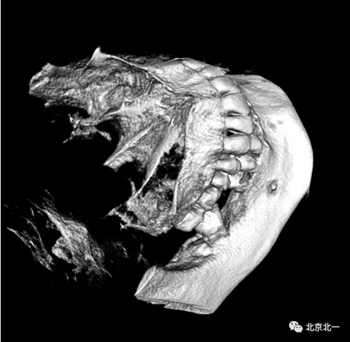

CBCT:骨量高度及寬度可, 48埋伏,低位阻生.37近中骨吸收

診斷:下頜牙列缺損, 48低位埋伏阻生 37 牙周炎

治療計(jì)劃:46種植, 同期拔除48 正畸扶正47.

北一種植王明老師總結(jié):本病例難點(diǎn)在于設(shè)計(jì)多學(xué)科治療。 治療周期拉長(zhǎng), 患者智齒低位, 拔除困難, 容易造成神經(jīng)麻木。 必須由經(jīng)驗(yàn)醫(yī)師主刀。 北一微創(chuàng)拔牙理念主張將牙齒進(jìn)行有絲分裂, 進(jìn)行智齒粉碎。 對(duì)工具要求較高。 較少患者痛苦。